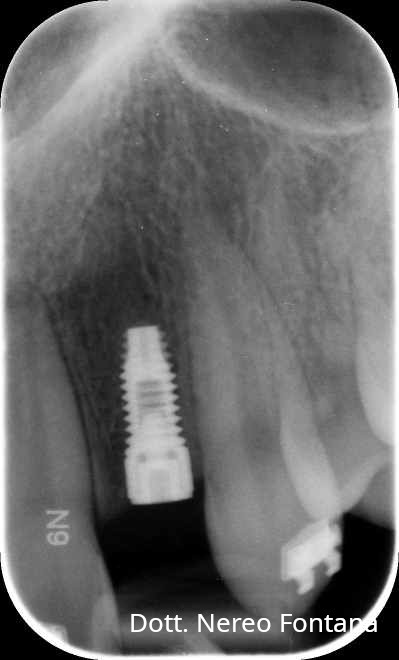

Abrasioni cervicali

Agenesia incisivi